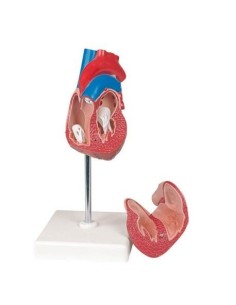

Du crâne en 22 parties à verrouillage magnétique aux modèles de colonne vertébrale, des modèles d'articulation aux modèles de cœur, chaque pièce de notre collection est conçue pour une immersion totale dans l'étude de l'anatomie humaine. Nos modèles, réalisés à partir de scans d'os réels, garantissent une expérience tactile authentique et une fidélité de poids presque identique aux originaux.

Indispensables aux étudiants comme aux professionnels, nos modèles anatomiques sont des outils pédagogiques qui permettent d'observer les structures anatomiques avec précision, en évitant les dissections ou les études invasives. Ils sont également utiles pour expliquer les pathologies aux patients, ce qui rend la communication plus efficace et permet de gagner un temps précieux.